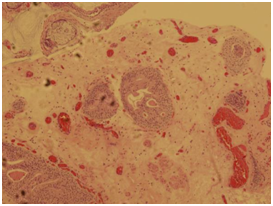

A complete blood count, liver function test, urine culture and PSA were all within normal ranges. Urine cytology revealed atypical cells. CT abdomen and pelvis with I.V contrast showed a 3.1 x 2.4 x 3 cm polypoidal mass of the trigone (Figure 1). Afterwards, the patient underwent cystoscopy which showed a solid florid mass extending from the trigone to the posterior wall of the urinary bladder, TURBT was carried out. The Histopathology slides showed cystitis cystica with cystitis glandularis (Colonic metaplasia) (Figure 2‒5).

Figure 3 Both figures 2, 3 show Cystitis glandularis-complex glandular structure lined by mucin producing cells connecting with the overlying transitional epithelium resembles colonic mucosa with goblet cells and mucin extravasation.

Figure 4 View of Cystitis cystica. Each of the epithelial nests has a central lumen.